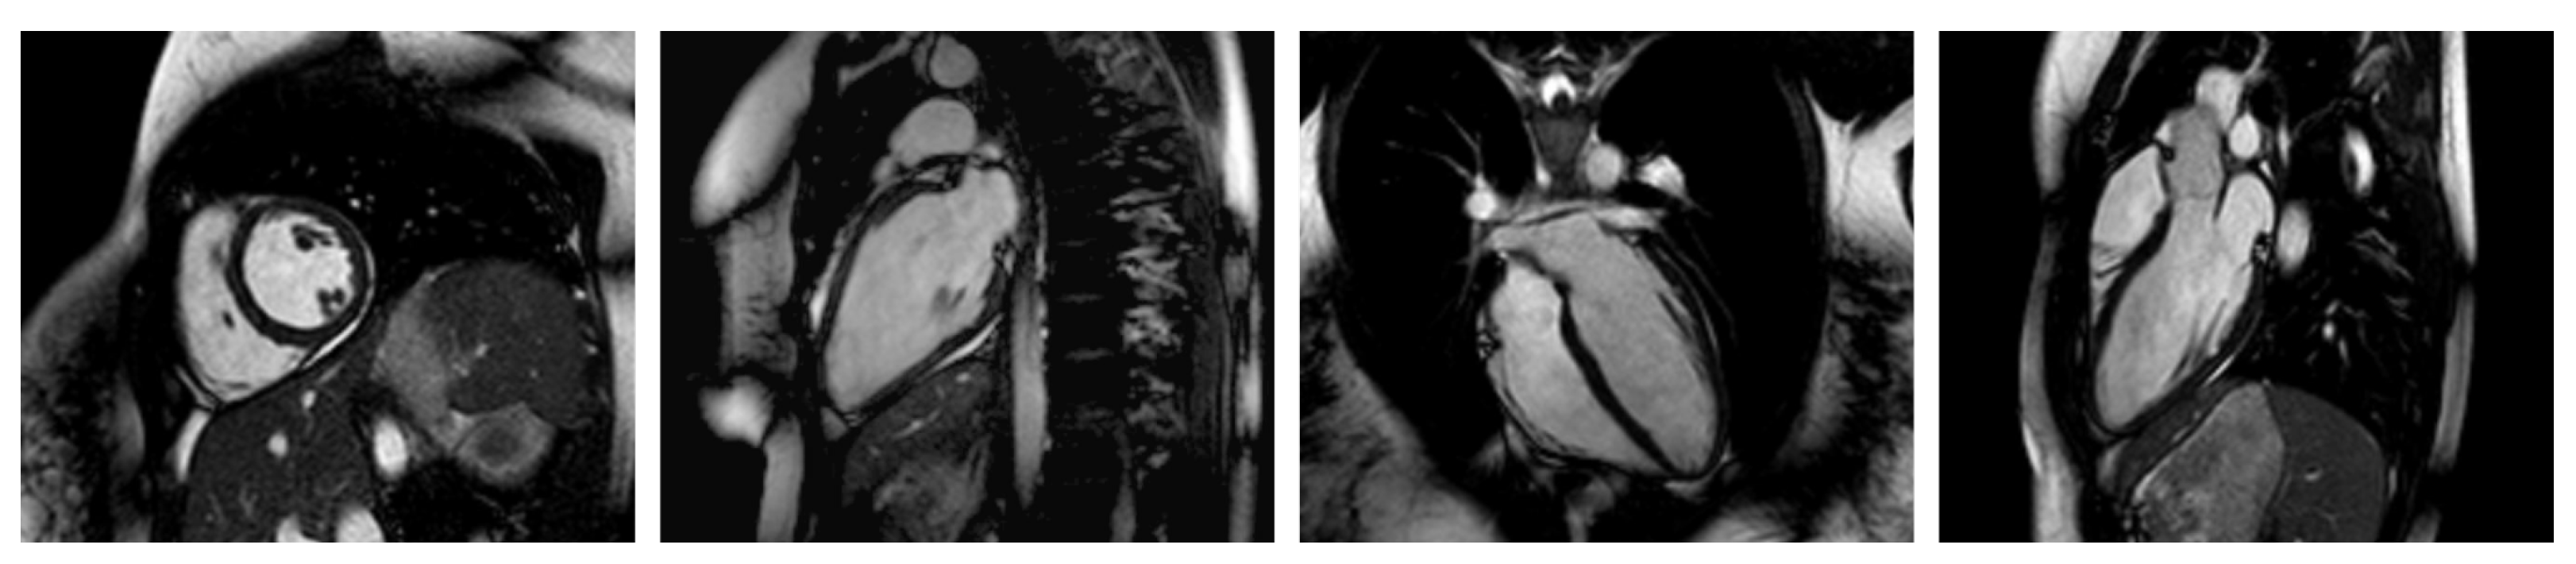

Appendix C. Example Images

- Short-axis images from the apex to the base at different stages of the cardiac cycle;

- Long-axis, two-chamber images at different stages of the cardiac cycle (heart beat);

- Long-axis, three-chamber images at different stages of the cardiac cycle;

- Long-axis, four-chamber images at different stages of the cardiac cycle.